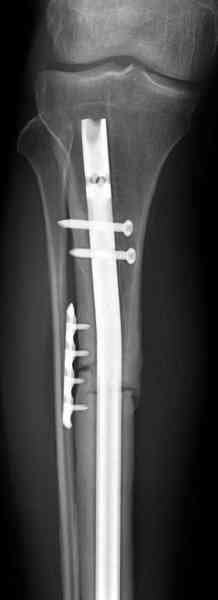

Спасибо за поздравления. Операция на самом деле довольно технологичная, все как-то удобно почти само получается.

>Заполняли ли чем-нибудь пространство между кейджем и штифтом?

Нет. Просвет внутри кейджа - 13 мм, штифт - 12 мм. Не так там и много пространства то есть. Но вопрос правильный, интересный, из разряда современных нерешенных проблем.

Не оригинальное, подход не раз был демонстрирован нас в стране проф. Анатолием Федоровичем Лазаревым (ЦИТО), который это называет "металлокаркасная пластика". У нас в институте в другом отделении он

помогал сделать несколько таких металлокаркасов, только, насколько я помню, без блокируемых стержней. А в мире эта методика довольно давно

применяется, хотя и не массово. Например, осенью прошлого года на конференции общества Кюнчера в Страсбурге было хорошее сообщение на эту тему. 17 больных, результаты уже до 5 лет.

The cages are commercially available but up to 10 cm. So we measured the needed length on x-rays, added 2 cm at both ends for sure that

the resected piece will include all, and resulted with 15 cm which one was ordered and individually made by the same factory. So yes, we made the gap to fit the cage.

gt> metal for long term support without biological augumentation?

The inner diameter of the tube is 13 mm, the nail was 12 mm, so not so much space to put something inside. Yes, this is really shaft endoprosthesis which i hardly ever would offer for a young football player. Though... Maybe we would when we collect some experience with this sort of implants to feel/prognose its strength in different settings.